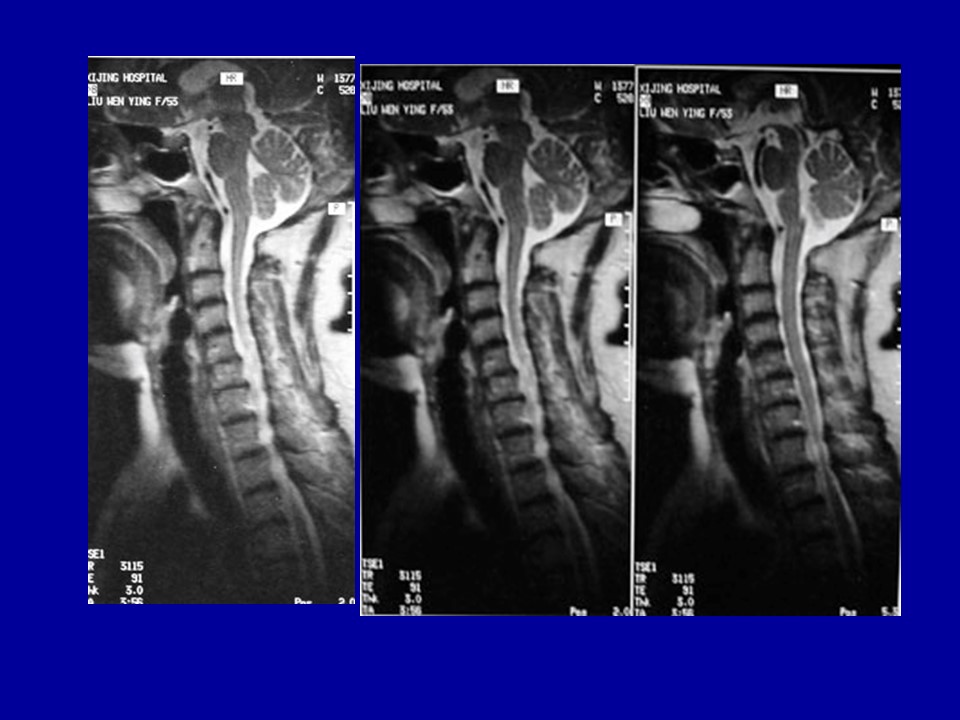

颈椎病的解剖及分型治疗PPT